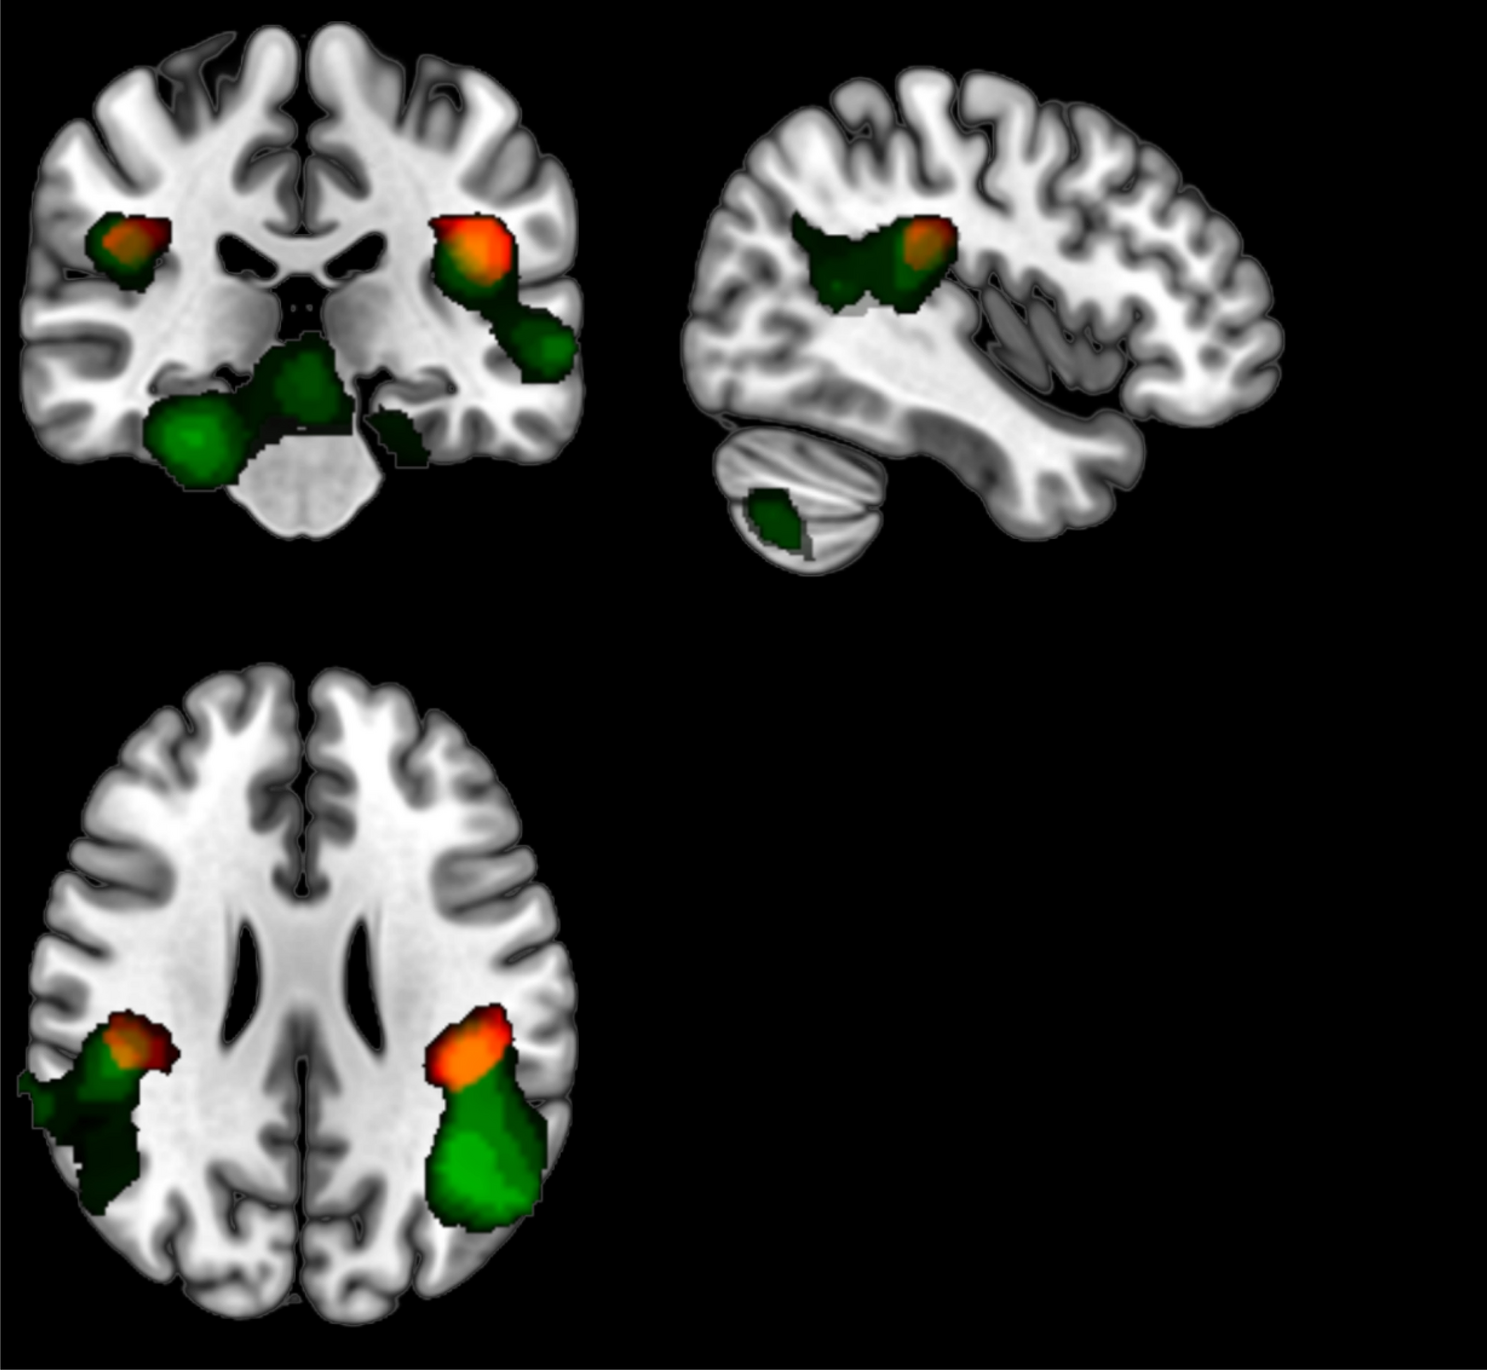

Figure 5

From: Respiratory function modulated during execution, observation, and imagination of walking via SII

The green areas show the result of the conjunction analysis Execution ∩ Observation, areas that resulted to be activated by both Execution and Observation conditions. The red areas show the result of GLM analysis using RR parameters as regressors during all three conditions (Execution, Imagination, and Observation). The yellow areas are the common areas that correspond with left and right parietal opercula, OP1 (SII).